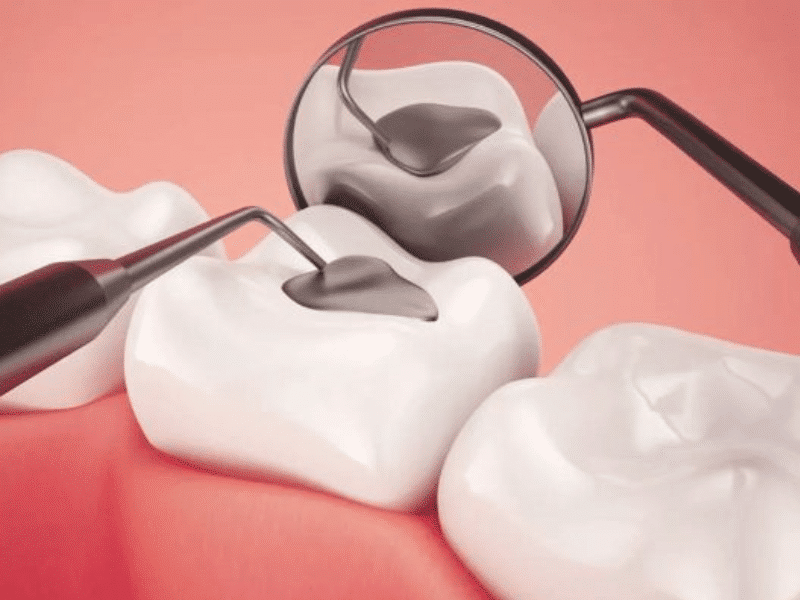

TRÁM RĂNG THẨM MỸ LÀ GÌ?

Đây là một phương pháp nha khoa nhằm phục hồi hình dạng và chức năng của răng. Những chiếc răng đã được trám sẽ có đảm bảo về hình dáng, màu sắc cũng như khả năng hoạt động.

Răng bị sâu

Răng bị sâu, lỗ sâu sẽ được làm sạch sau đó tiến hành trám